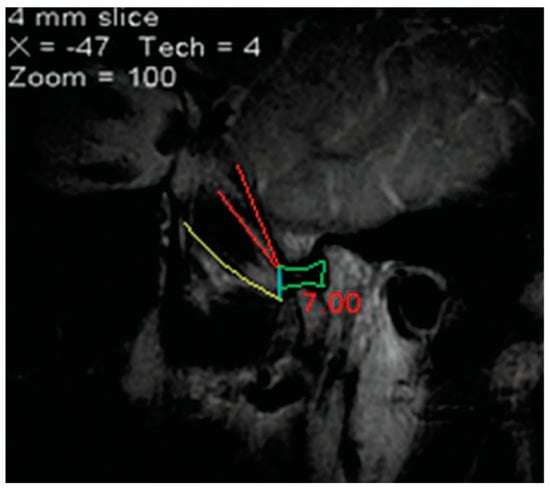

The Accessory Pterygoid Fovea